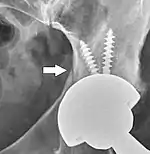

Post-operative projectional radiography is routinely performed to ensure proper configuration of hip prostheses.

The direction of the acetabular cup influences the range of motion of the leg, and also affects the risk of dislocation.[6] For this purpose, the acetabular inclination and the acetabular anteversion are measurements of cup angulation in the coronal plane and the sagittal plane, respectively.

On radiography, it is normal to see thin radiolucent areas of less than 2 mm around hip prosthesis components, or between a cement mantle and bone. However, these may still indicate loosening of the prosthesis if they are new or changing, and areas greater than 2 mm may be harmless if they are stable.[20] The most important prognostic factors of cemented cups are absence of radiolucent lines in DeLee and Charnley zone I, as well as adequate cement mantle thickness.[21] In the first year after insertion of uncemented femoral stems, it is normal to have mild subsidence (less than 10 mm).[20] The direct anterior approach has been shown to itself be a risk factor for early femoral component loosening.[22][23][24]